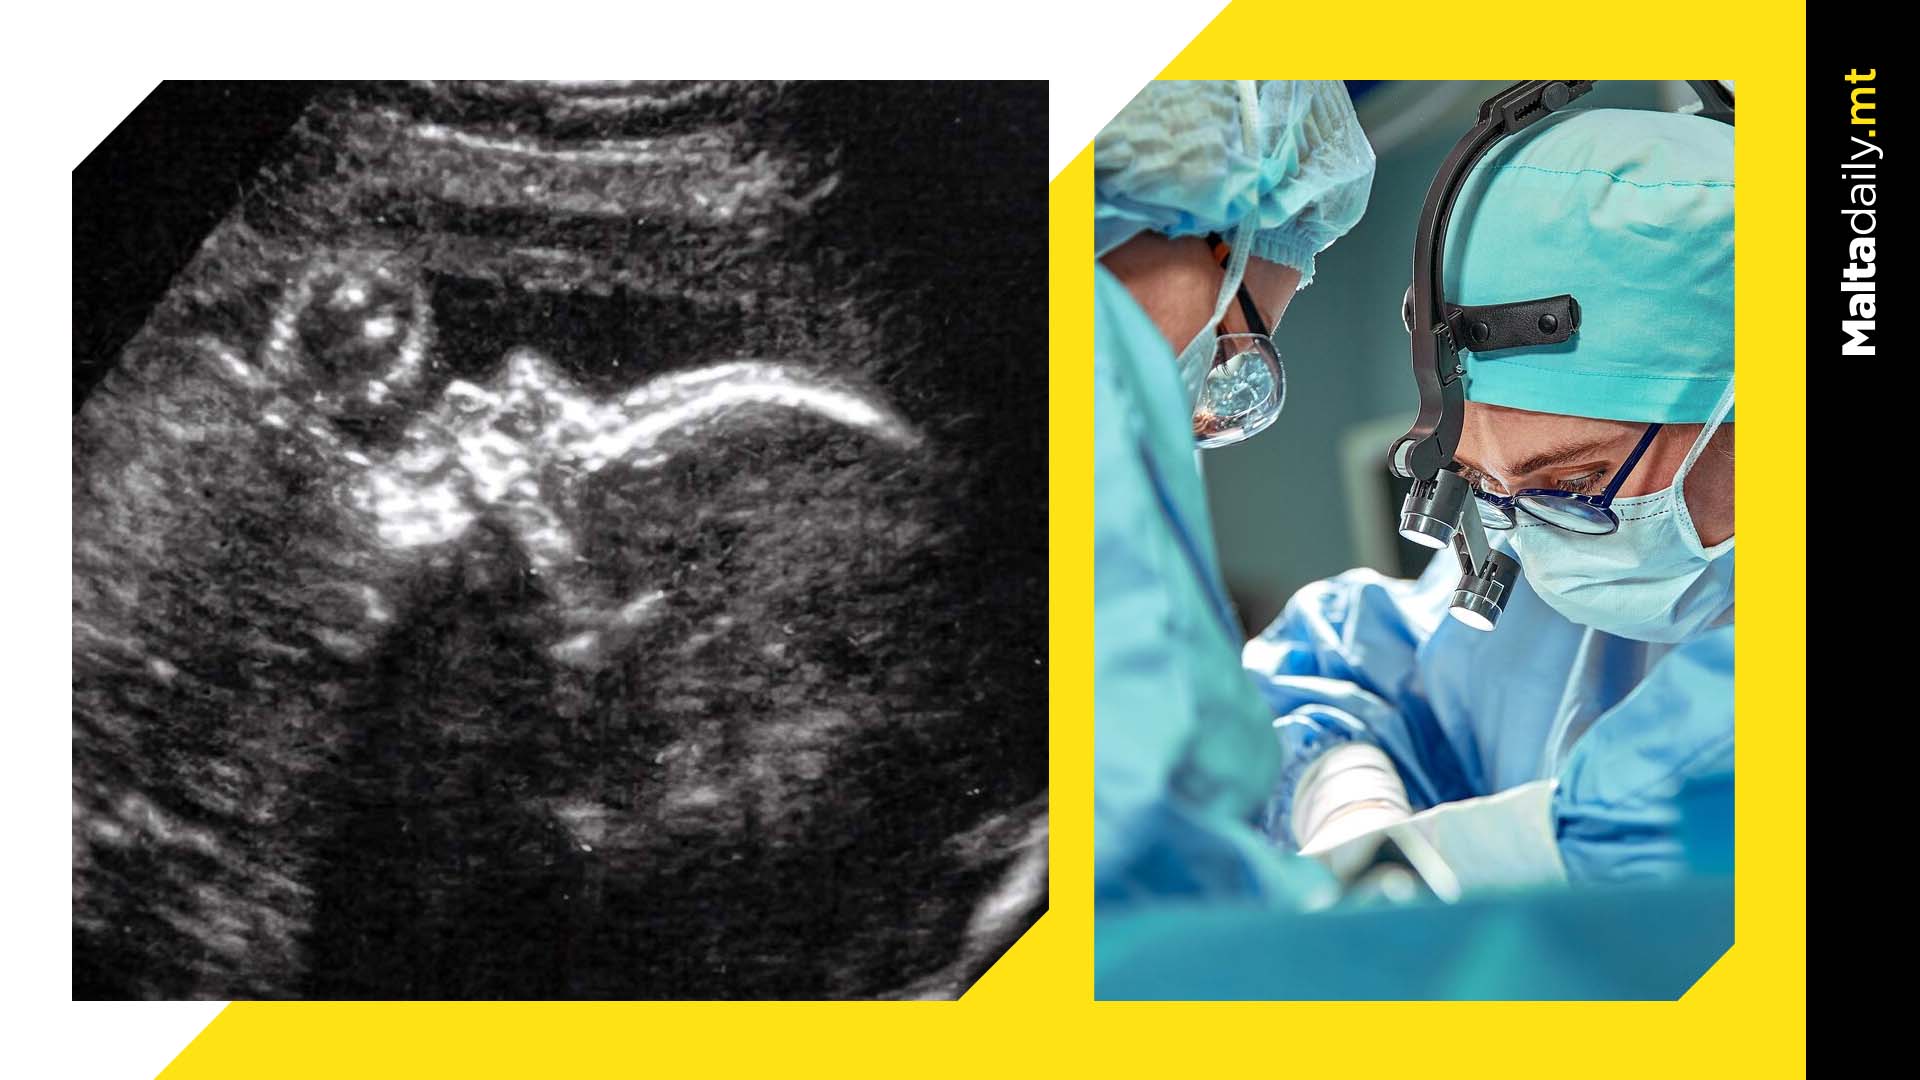

Doctors have just performed a first-of-its-kind brain surgery on a baby still inside the womb in order to fix deadly damage to blood vessels and thus potentially eliminate heart failure or stroke in the future.

This was the first treated patient in a clinical trial that is underway at Boston Children’s Hospital and Brigham and Women’s Hospital, along with the oversight of the US FDA.A rare pre-natal condition known as Vein of Galen Malformation (VOGM) causes foetuses to have arteries which carry high-pressure blood whilst connected to one of the main veins deep at the base of the brain.

The US team utilised ultrasound to carry out the procedure, with the baby currently still in the womb of a 34 week old pregnant woman.